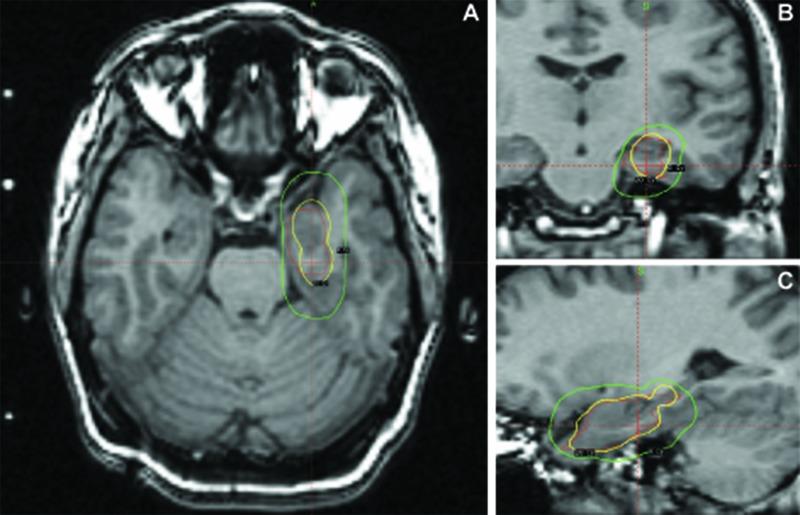

Stereotactic radiosurgery (SRS) is a promising treatment for medically intractable mesial temporal lobe epilepsy. SRS for epilepsy has had an acceptable safety profile with reports of radiation-induced vascular malformations confined to central nervous system pathologies with prominent angiogenesis - namely, primary brain tumors, metastases, and arteriovenous malformations. Theoretical risks for radiation-induced lesions following radiosurgery for epilepsy have yet to be established. Of 13 patients treated in a pilot trial for medial temporal lobe epilepsy, one developed multiple delayed radiation-induced cavernous malformations following radiosurgery. This patient received a prescription dose of 20 Gy delivered to the amygdala, anterior hippocampus, and parahippocampal gyrus. Eight years following treatment, computed tomography imaging demonstrated an evolving hyperdensity in the mesial temporal lobe. Magnetic resonance imaging confirmed multiple T2 hypointense lesions with a mixed-signal intensity core in the left parahippocampal gyrus and anterior temporal lobe. The patient was initially managed conservatively. However, recurrent hemorrhage ultimately caused an acute deterioration in mental status, aphasia, and hemiparesis, necessitating surgical resection. Pathology confirmed radiation-induced cavernous malformations. This represents the first case of a radiation-induced vascular lesion as a long-term sequela of radiosurgery for epilepsy and illustrates the potential for this complication even when low doses are used in patients without angiogenic lesions. Optimal timing and indications for surgical resection of radiation-induced cavernous malformations prior to the development of neurologic symptoms warrant further refinement. Long-term vigilance and clinical monitoring are required.

立体定向放射外科手术(SRS)是治疗药物难治性内侧颞叶癫痫的一种有前景的方法。用于癫痫的SRS具有可接受的安全性,有报告称辐射诱发的血管畸形局限于具有显著血管生成的中枢神经系统病变,即原发性脑肿瘤、转移瘤和动静脉畸形。癫痫放射外科手术后辐射诱发病变的理论风险尚未确定。在一项内侧颞叶癫痫的试点试验中治疗的13例患者中,有1例在放射外科手术后出现了多个延迟性辐射诱发的海绵状畸形。该患者接受了20 Gy的处方剂量,照射杏仁核、前海马体和海马旁回。治疗8年后,计算机断层扫描成像显示内侧颞叶出现逐渐发展的高密度影。磁共振成像证实左侧海马旁回和颞叶前部有多个T2低信号病变,核心为混合信号强度。患者最初采用保守治疗。然而,反复出血最终导致精神状态急性恶化、失语和偏瘫,需要进行手术切除。病理证实为辐射诱发的海绵状畸形。这是首例作为癫痫放射外科手术长期后遗症的辐射诱发血管病变,表明即使在没有血管生成病变的患者中使用低剂量时,这种并发症也有可能发生。在神经症状出现之前,手术切除辐射诱发的海绵状畸形的最佳时机和适应证有待进一步完善。需要长期的警惕和临床监测。